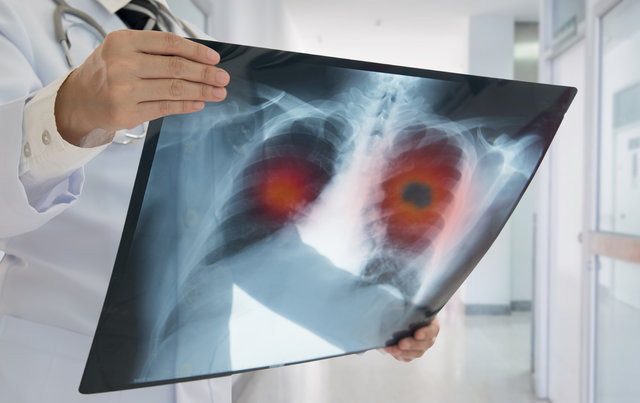

“Akciğer kanserlerinin yüzde 5'i erken evrede yakalanırsa tama yakın tedavi edilebilir. Geri kalanlarda ise yapılan tedavilerle hastalıksız dönemin uzatılması hedeflenir.

Tanı konduktan sonra hastalığın evresine göre cerrahi, kemoterapi ve radyoterapi yöntemleri uygulanır” diyen Kılınç, riski azaltmanın en etkili yolunun sigaradan kurtulmak olduğunu vurguladı: